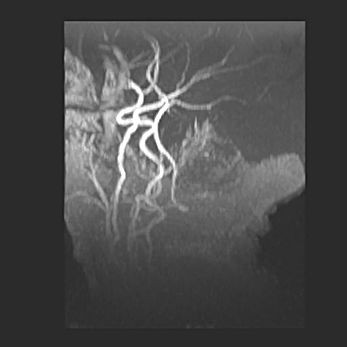

Подострая гематома правой гемисферы мозжечка.

Наружная гидроцефалия.

Возраст: 15 дней

Вес: 3100 г

Пол: женский

Окружность головы: 37 см

Срок гестации: 35-36 недель

При открытой наружной форме гидроцефалии у новорожденных расширяются и переполняются субарахноидные пространства.

Кровоизлияния в мозжечок имеют две клинико-анатомические формы: полушарные гематомы и кровоизлияния в червь.

К появлению этой патологии может привести: повреждения головного мозга, возникающие в результате асфиксии и гипоксии плода при беременности, или травмы во время родов. Редко гематома мозжечка может быть результатом первичной коагулопатии и сосудистой мальформации, диссеминированном внутрисосудистом свертывании, изоиммунной тромбоцитопении.